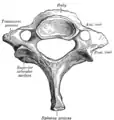

الفقرة العنقية الثانية من أعلى أو "المحور".

يكون جسم الفقرة العنقية أصغر من جسم الفقرة الصدرية (وذلك لأن الوزن الذي يتحمله أقل من الوزن الذي تتحمله الفقرة الصدرية). وشوكة الفقرة العنقية تكون أيضا أصغر ومشقوقة. أما النتوء المستعرض ففيه ارتفاع أمامي وخلفي، وثقب (بالإنجليزية: foramen transversarium) . في بعض الناس يكون هناك ضلع "عنقي" مرتبط بالفقرة العنقية السابعة وقد يسبب انسدادا للشرايين والأوردة والأعصاب وكل الأعراض الناتجة من ذلك.